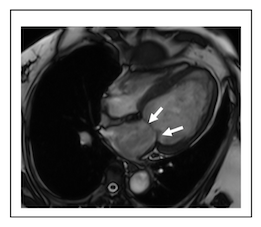

12-37 図中の矢印で示す弁を選択して下さい。(正解 2 つ)